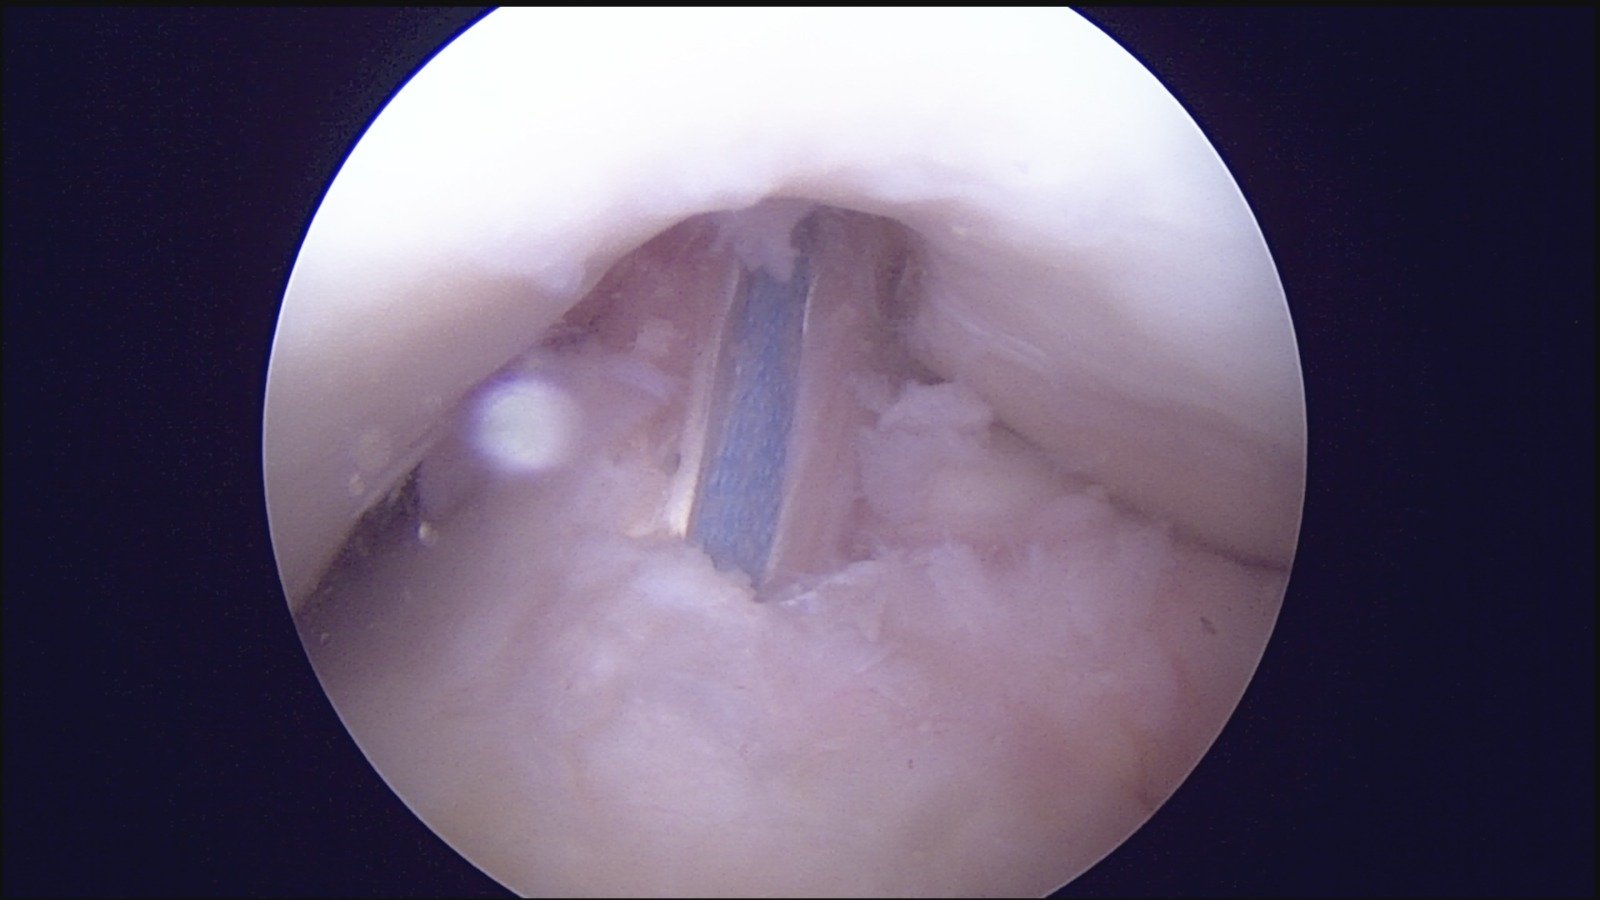

GalleryShoulder rotator cuff repair Meniscus root repair Meniscus repair Bankart repair for recurrent shoulder dislocation ACL reconstruction Machines Instruments